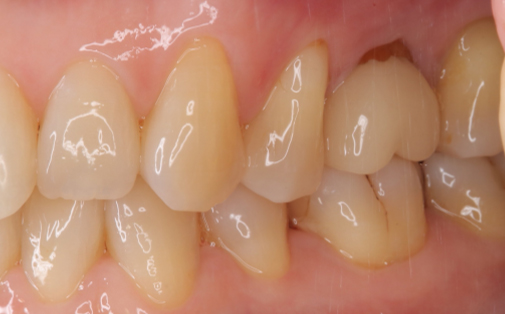

抜歯した親知らずを移植(1)

Before

After

左上の親知らずの歯を移植しました。20代前半の症例です。

ご自身の歯のため親和性が高く、移植後も不自由なく機能しています。